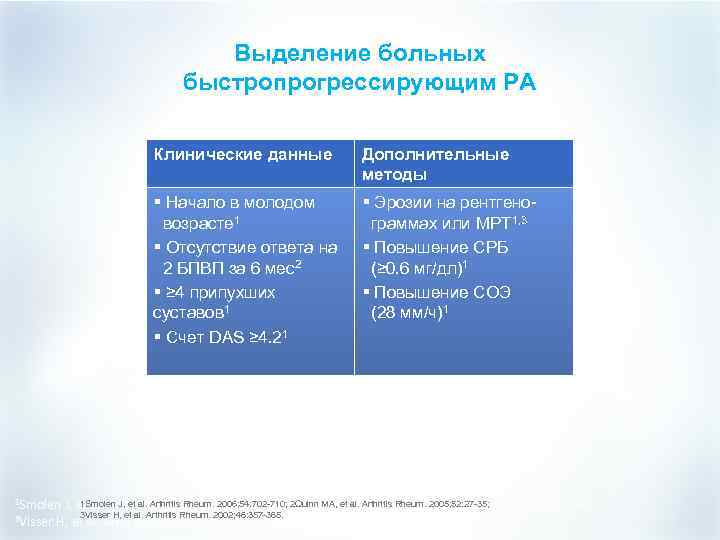

Выделение больных быстропрогрессирующим РА Клинические данные § Начало в молодом возрасте 1 § Отсутствие ответа на 2 БПВП за 6 мес2 § ≥ 4 припухших суставов 1 § Счет DAS ≥ 4. 21 1 Smolen Дополнительные методы § Эрозии на рентгенограммах или МРТ 1, 3 § Повышение СРБ (≥ 0. 6 мг/дл)1 § Повышение СОЭ (28 мм/ч)1 1 Smolen J, et al. Arthritis Rheum. 2006; 54: 702 -710; 2 Quinn MA, et al. Arthritis Rheum. 2005; 52: 27 -35; 3 Visser H, et al. Arthritis Rheum. 2002; 46: 357 -365.

Выделение больных быстропрогрессирующим РА Клинические данные § Начало в молодом возрасте 1 § Отсутствие ответа на 2 БПВП за 6 мес2 § ≥ 4 припухших суставов 1 § Счет DAS ≥ 4. 21 1 Smolen Дополнительные методы § Эрозии на рентгенограммах или МРТ 1, 3 § Повышение СРБ (≥ 0. 6 мг/дл)1 § Повышение СОЭ (28 мм/ч)1 1 Smolen J, et al. Arthritis Rheum. 2006; 54: 702 -710; 2 Quinn MA, et al. Arthritis Rheum. 2005; 52: 27 -35; 3 Visser H, et al. Arthritis Rheum. 2002; 46: 357 -365.